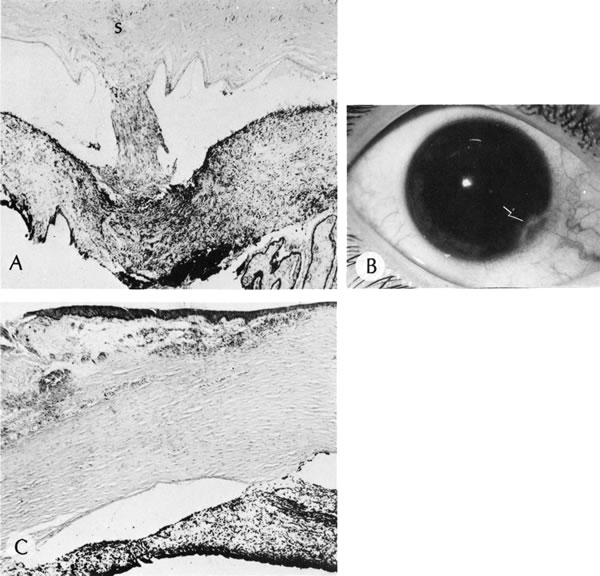

PETERS' ANOMALY

Peters' anomaly includes absence of central corneal endothelium, Descemet's membrane, and variable amounts of corneal stroma (Fig. 4). In most cases Bowman's membrane also is absent. Peters' anomaly may be caused by primary dysgenesis of the corneal endothelial mesoderm, primary dysgenesis of keratocyte and endothelial neural crest mesoderm, or secondary endothelial degeneration due to late anterior displacement of a normally developed crystalline lens.48 In addition, it has been suggested that abnormal apposition of an ectopic lens to the developing cornea during the second or third month of gestation may be the cause of exceptional cases of peripheral Peters' anomaly.49

Fig. 4. Peters' anomaly. A. Note the central corneal scar in the right and left eyes. The lens was adherent to the back of the corneal scar. Iris abnormalities also were present. B. The anterior segment shows a posterior corneal defect, a “top hat” appearance of the lens, and total adherence of the anterior surface of the iris to the cornea. C. High magnification shows termination of the endothelium and Descemet's membrane (arrow), corneal thinning, and localized absence of Bowman's membrane. The lens (lower left) is artifactually separated from the cornea. D. A PAS-positive membrane (lens capsule) is shown (top) adherent to the posterior corneal surface (arrow). The lens cortex (c) is artifactually separated from the rest of the lens (bottom). (Courtesy of SEI Photoarchives.) (B–D modified from Scheie HG, Yanoff M: Peter's anomaly and total posterior coloboma of retinal pigment epithelium and choroid. Arch Ophthalmol 87:525, 1972.)

Associated anterior segment anomalies include corectopia, iris hypoplasia, anterior polar cataract or other lens abnormalities, and iridocorneal adhesion. (Fig. 5) Corneal perforations secondary to Peters' anomaly have been reported at birth.50,51 Systemic anomalies include Potter's syndrome (agenesis of the urinary tract) and intestinal malrotation.52–54 Generally, no specific inheritance pattern has been noted, although a family that had an autosomal dominant inheritance pattern has been reported.55

Fig. 5. Peters' syndrome complicated by buphthalmos. The corneal anterior segment of the right eye has expanded because of the influence of increased intraocular pressure on scleral tissue that is still elastic in young people.

Histopathologic findings include absence of Descemet's membrane, corneal endothelium, and usually Bowman's membrane, as well as thinning of corneal stroma. The defects in Descemet's membrane, although usually single and central, may be multiple and isolated to the periphery or may be limited to an area of adhesion of iris.56 Descemet's membrane has been found to have embryonal ultrastructural characteristics combined with attenuated endothelium.57 The corneal stromal lamella are more irregular and closely packed when compared with normal. Immunohistochemical markers indicate that a normal complement of collagens type I, III, IV, V, and VI occurs in Peters' anomaly; however, an increased concentration may occur of the adhesive protein fibronectin, which is known to play a role in the embryologic development of the cornea.58–60